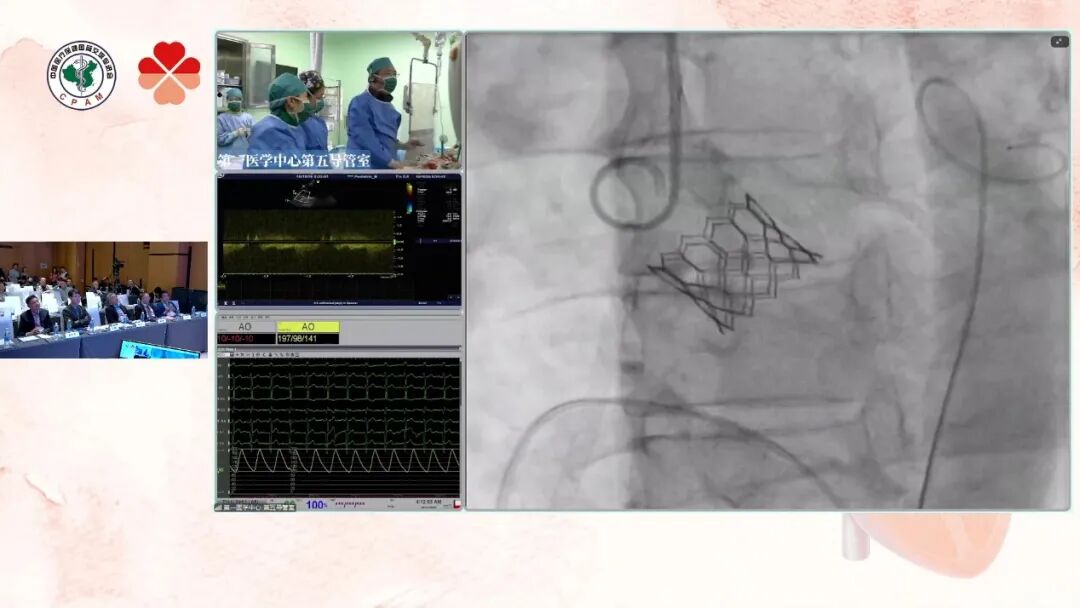

患者为61岁女性,主诉活动后胸闷1年,近期症状加重。既往病史包括冠心病6年、甲亢26年、高血压2年及家族性高胆固醇血症。术前超声提示主动脉瓣重度狭窄伴中度关闭不全,同时存在先天性房间隔缺损(筛孔型)及二尖瓣轻度关闭不全。术前CT分析显示患者瓣环较小,瓣叶中度钙化且分布均匀,双冠开口高度临界,存在一定冠脉阻塞风险,为手术操作增加了挑战。术中以右股为主入路,植入20# 瓣膜,减容1mL,球囊匀速、缓慢充盈并足量保压5秒后释放瓣膜。随后行球囊后扩,瓣膜充分展开、位置精准。术后造影显示瓣膜位置良好、形态正常,手术顺利完成。

瓣膜释放成功